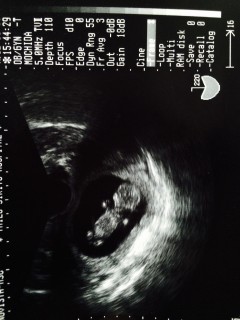

初めて心拍音を聴きました。 2週間前は3センチ半だったのに、今回は6.2センチ。 姿もとっても可愛らしい。 このまま無事に育ってね。(*^_^*)